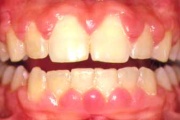

Krooniline gingiviit

Äge krooniline gingiviit

igemete veritsus kroonilise gingiviidiga patsiendil

Gingiviit ehk igemepõletik